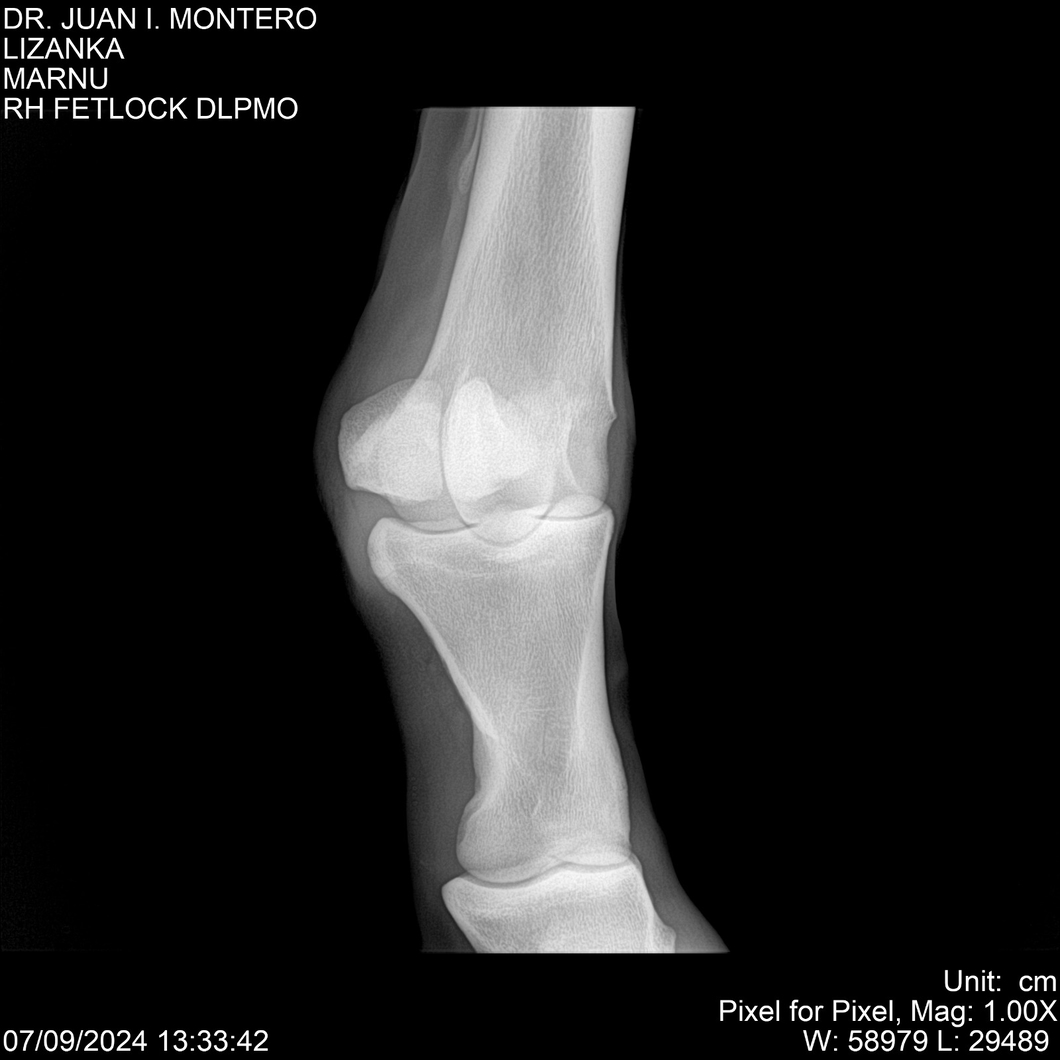

LOTE 18, LIZANKA Lote Anterior Volver al remate Lote Siguiente Ficha Contacto Montevideo - Ficha del Lote Identificador: #282512 Categoría: Yeguarizos Montevideo - 62 Visualizaciones ClicData Contacto Empresa: Abelenda N. R., Walter Hugo Nombre*: Teléfono* : E-mail* : Mensaje Enviar Registrese gratis Este contenido Exclusivo está disponible sólo para usuarios registrados Ingresar